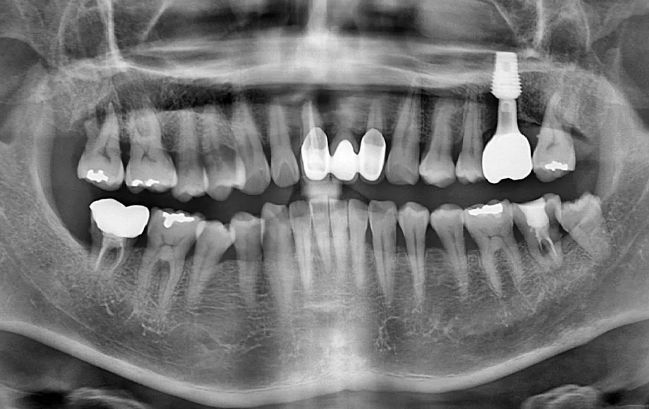

50대 남성, 원데이 앞니 임플란트